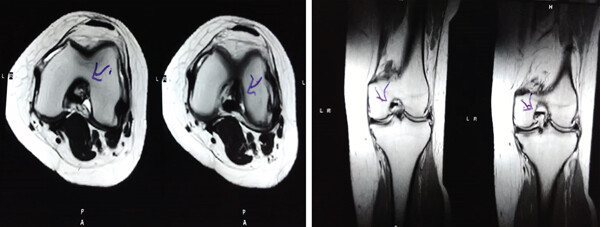

MRI檢查發(fā)現(xiàn)半月板損傷處修復(fù):3D MRI 顯示 2 年時(shí)半月板撕裂難以辨別。

影像學(xué)檢查:4例MM皮瓣撕裂患者在治療前后交界區(qū)中央?yún)^(qū)域出現(xiàn)缺損,但其中2例患者該區(qū)域完全恢復(fù)穩(wěn)定光滑狀態(tài),另2例患者該區(qū)域部分恢復(fù)。治療前后交界區(qū)中央?yún)^(qū)域皮瓣撕裂的關(guān)節(jié)鏡評分為0.3±0.5,治療后為4.3±2.1,治療后評分顯著升高。2例患者原有放射狀MM撕裂在治療一年后愈合。